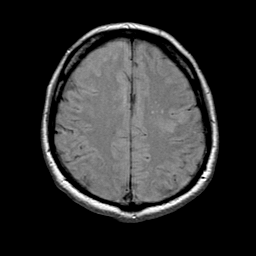

MR Study #1 -- Slice #17

Tour 1: Next/Previous/Start: On the next lower slice, extension of the infarct into white matter is seen.

[Home][Help][Clinical][Tour 1] Slice 17